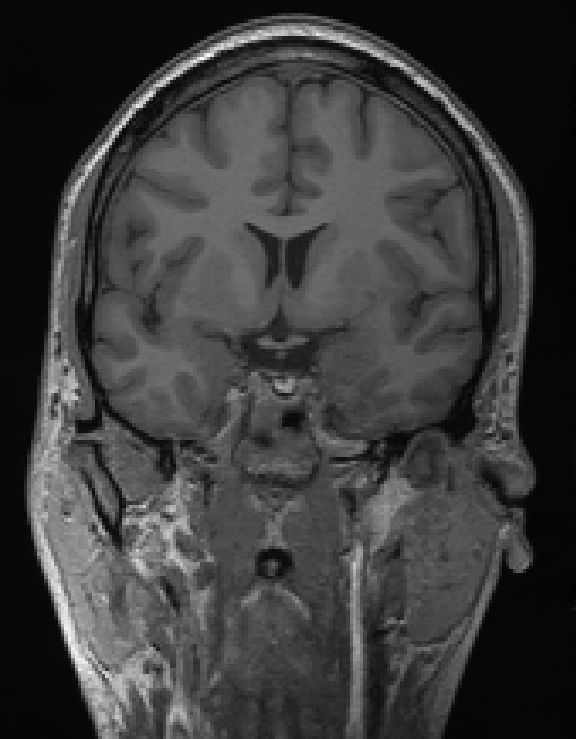

FDK

Our Unrolled[3D] framework

Illustration of our reconstruction method on real 3D cone-beam data. On the left, axial slice with [30/1200] views, and on the right, vertical slice with [30/1200] views. Our method significantly reduces the streaking artifacts and noise compared to the standard FDK reconstruction, while preserving fine details.